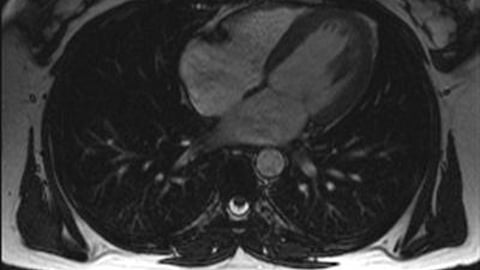

The collaboration integrates Konica Minolta’s cloud-based Exa Enterprise platform with ASCEND Cardiovascular’s specialized multimodality cardiovascular imaging workflows. This combined platform aims to give clinicians access to a full, longitudinal patient imaging record — overcoming the data silos and systemic limitations often found with broader, non-specialized imaging systems.

The unified solution will support a wide range of cardiovascular care needs, including invasive and non-invasive procedures, for both adult and pediatric patients.